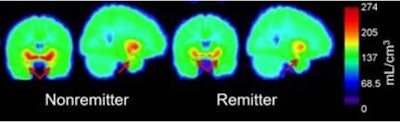

The study included 31 healthy controls and 26 medication-free patients with MDD who received a PET scan using C-11 DASB. The MDD subjects then received eight weeks of standardized therapy with escitalopram.

Ananth and colleagues found a significant difference in amygdala binding, with medication-free patients showing 11% less amygdala binding than the controls. They suggested that 5-HTT amygdala binding should be studied further as a possible biomarker for remission after treatment with escitalopram.

"Our results indicate that patients who found relief following escitalopram treatment had less 5-HTT protein before treatment began," Ananth said. "This is exciting because it suggests that pretreatment neurobiology can be used to predict response to treatment, potentially preventing ineffective treatment trials."